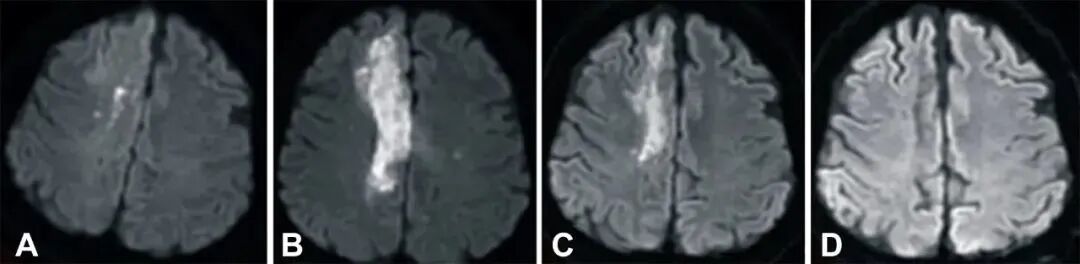

中风后 2 小时、8 天进行的弥散加权成像(DWI)显示右侧放射冠有梗死(白色强度增加),3 个月后开始退散,6 个月后消失(A到D)